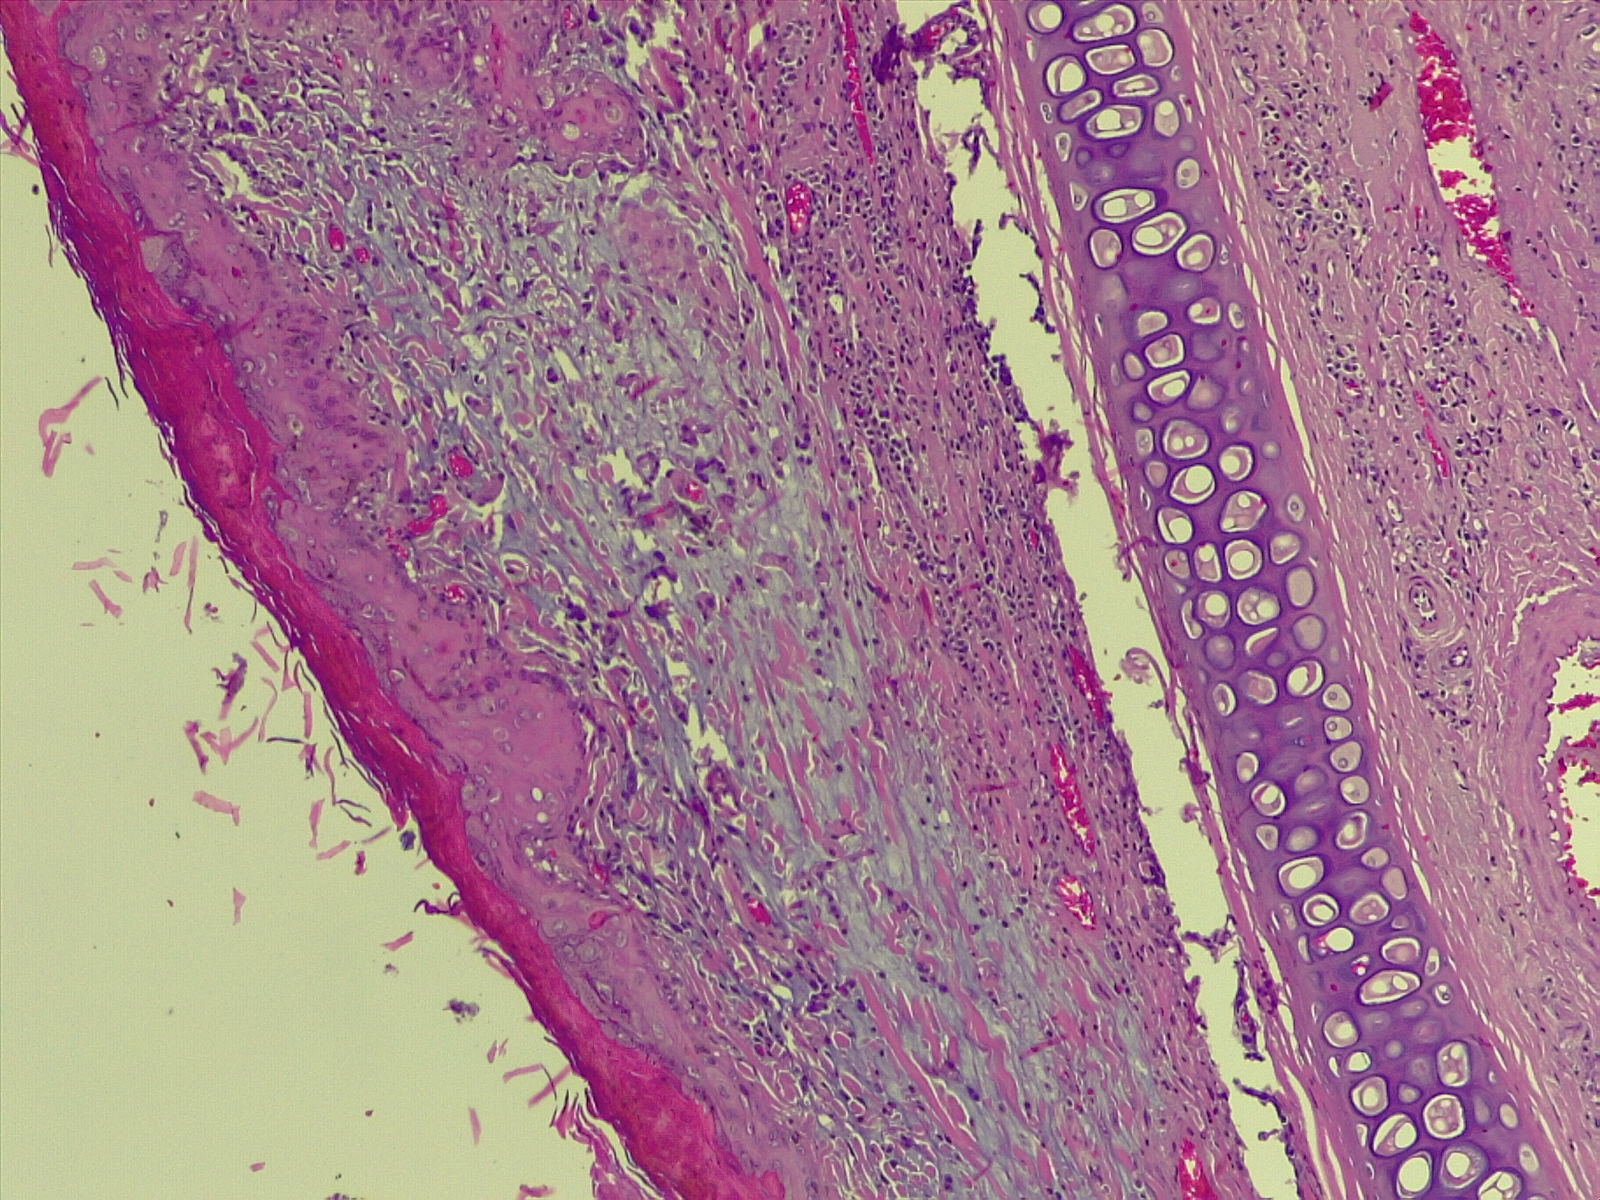

A vírus a csípést követően a bőrben elszaporodik, majd bekerül a véráramba, és a belső szervekben egy ismételt szaporodás után végül újra a bőrbe jut. Itt kialakulnak a klasszikus elváltozások, amelyek lényegében göbképződéssel járó gyulladásnak felelnek meg. A kórokozó hatására az irharétegben kialakulnak az ún. myxomasejtek (a myxomasejtek a mesenchyma-sejtekből kialakuló, nagy, sokszor nyúlványokkal rendelkező, módosult sejtek, amelyek tipikusak a myxomatosisban elhullott állatok irha rétegében) is. Az eddigi megfigyeléseink szerint a göbök a legintenzívebben a szemhéjakon, a száj körüli bőrképletekben és a genitáliákban jelennek meg, amelyet súlyosfokú vizenyő is kísér. Szövődményként gennyes jellegű orrgyulladás, bakokban tasakgyulladás és ivartól függetlenül kötőhártya-gyulladás is fellép, ami az érintett egyedek tájékozódási zavarával is jár. Mindennek eredményeként az állat lényegében képtelenné válik az életben maradásra: táplálkozása akadályozott, könnyű prédává válik a ragadozók számára és közútra tévedve gyakran a forgalom áldozatává válik.

Kutatóink a vizsgálataik során a jellegzetes kórbonctani és kórszövettani elváltozások mellett, PCR vizsgálattal a vírus örökítő anyagát is ki tudták mutatni. A vírus genom-szekvenálását követően pedig teljes bizonyossággal beigazolódott a kórkép okozta elhullás. Eredményeinket az országban elsőként az Acta Veterinaria Hungarica tudományos folyóirat hasábjain közöljük, amit a folyóirat már közlésre be is fogadott.